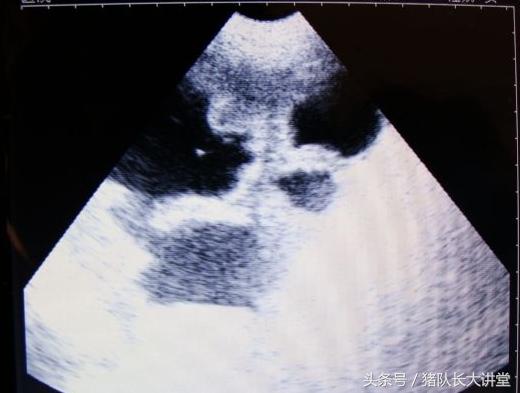

23天的B超图

2、这里只说下B超因为本人用的也比较多;

27天图

A、可以较为准确的测出是不是有小猪,具体使用办法,根据说明使用,大家也可以提出问题;注意,一般你检测有的就是有了,单是检测没有的时候应该多观察;

中间的黑球是初期胚胎